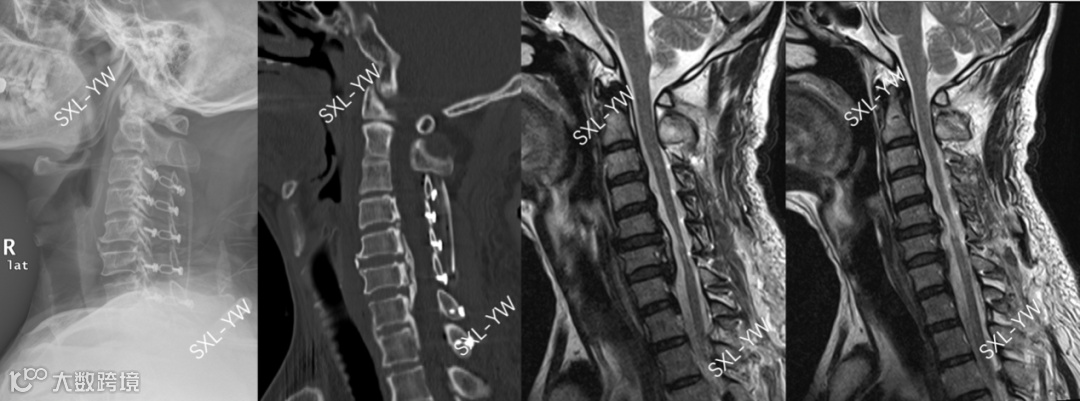

图12 K线与PCS评分的正面碰撞之一,术前影像

上述病例,如果参考K线理论,该OPLL患者K线阴性,单开门术后脊髓漂移将不充分、神经功能恢复将不理想,建议放弃单开门手术,行前路减压固定融合术或后路矫形内固定融合术。但是,如果参考我们的PCS评分,该患者得分15分,单开门术后神经功能恢复良好的可能性大,单开门手术的意义非常大。PCS评分建议手术节段为:C3-T1(得分区域)。

不同的指导意见,截然不同的治疗方法。采用K线做术前指导,患者需要接受创伤大、并发症多、后遗症多的融合手术。采用我们的PCS评分做术前指导,患者能接受到创伤小、并发症少、后遗症少的非融合手术。融合手术与非融合手术,该如何抉择?

图13 K线与PCS评分的正面碰撞之一,术后影像。C3-T1单开门术后脊髓获得充分漂移